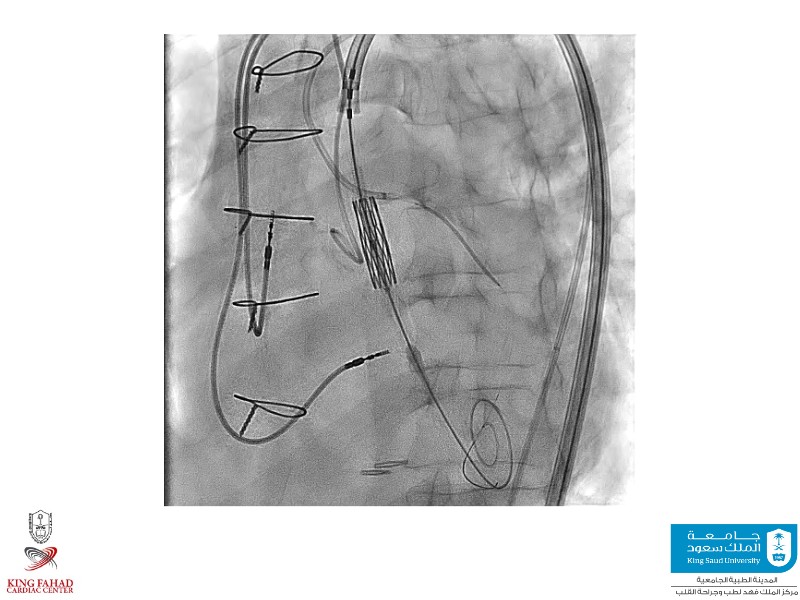

This session helps you anticipate and address complex scenarios such as mitral valve-in-valve, TAV-in-SAV, and valve-in-valve-in-valve procedures. Learn from expert case discussions that explore procedural strategies, technical challenges, and best practices to optimize outcomes in redo structural heart interventions.

- To anticipate and manage second valve scenarios with SAPIEN 3 Ultra RESILIA, including mitral valve-in-valve, TAV-in-SAV, and TAV-in-TAV

- To understand procedural strategies and challenges in complex redo scenarios using SAPIEN 3 Ultra RESILIA